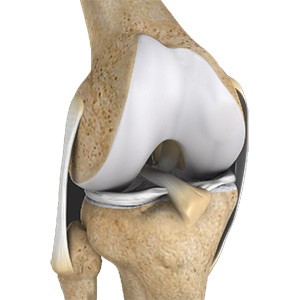

Chondral or Articular Cartilage Defects

The articular or hyaline cartilage is the tissue lining the surface of the two bones in the knee joint. Cartilage helps the bones move smoothly against each other and can withstand the weight of your body during activities such as running and jumping. Articular cartilage does not have a direct blood supply to it, so has less capacity to repair itself.